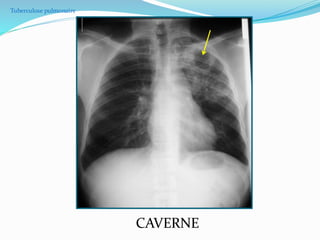

TUBERCULOSE PULMONAIRE

 2.Tuberculose post-primaire : condensation

pulmonaire + ou – excavation (NB: adénomégalie rare)

 Segment apical et postérieur des lobes supérieurs.

 Segment apical d`un lobe inférieur.

Condensations

pulmonaires des deux

sommets

Micronodules

et

caverne

Opacité calcifiée du LSG: cicatrice possible